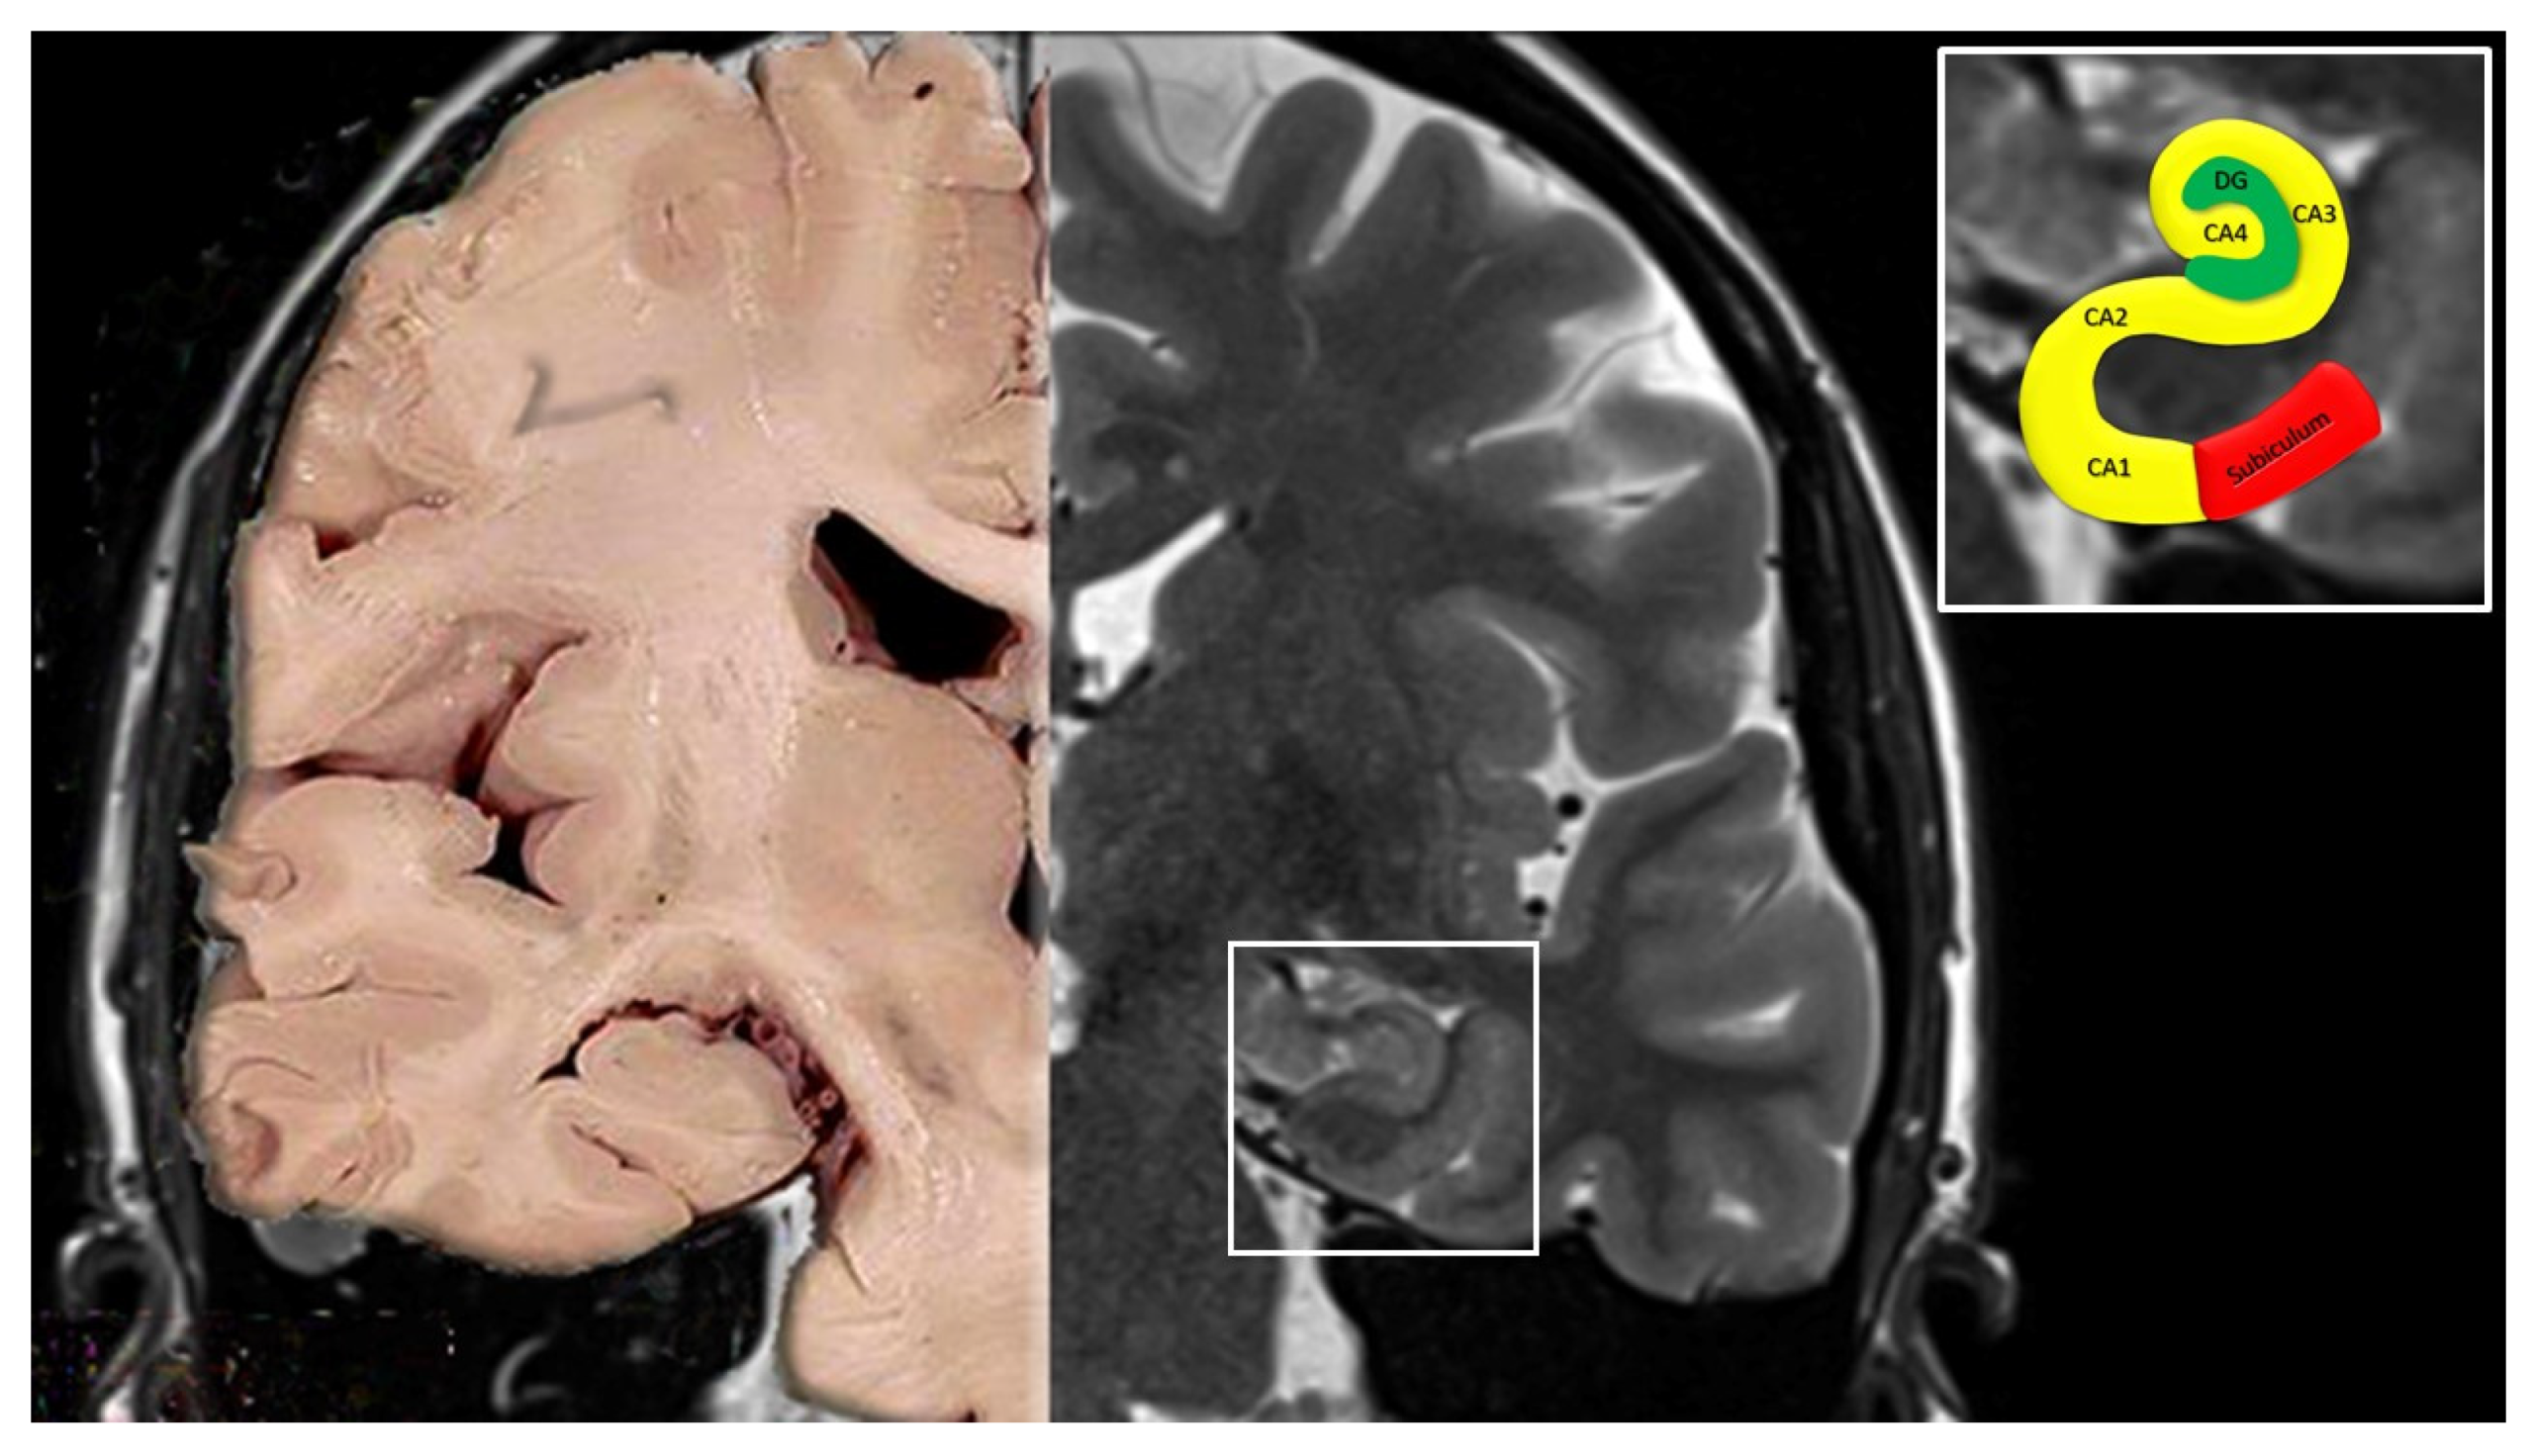

The hippocampus, especially the CA1 region, is highly sensitive to:

- Reduced blood flow

- Venous congestion

During a Valsalva maneuver:

- Transient dysfunction of hippocampal neurons occurs

- This leads to temporary inability to form and retrieve memories

Importantly, this is functional impairment, not permanent brain damage.